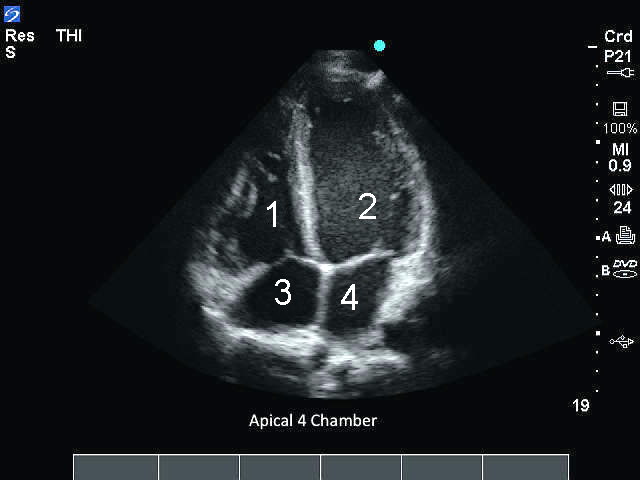

M-Turbo: Apical de 4 cámaras

1. Ventrículo derecho (VD)

2. Ventrículo izquierdo (VI)

3. Aurícula derecha (AD)

4. Aurícula izquierda (AI)